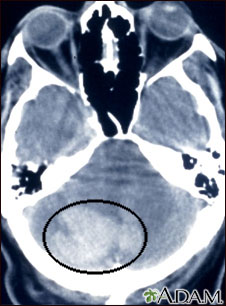

Intracerebellar hemorrhage - CT scan

Intracerebellar hemorrhage shown by CT scan. This hemorrhage followed use of t-PA.